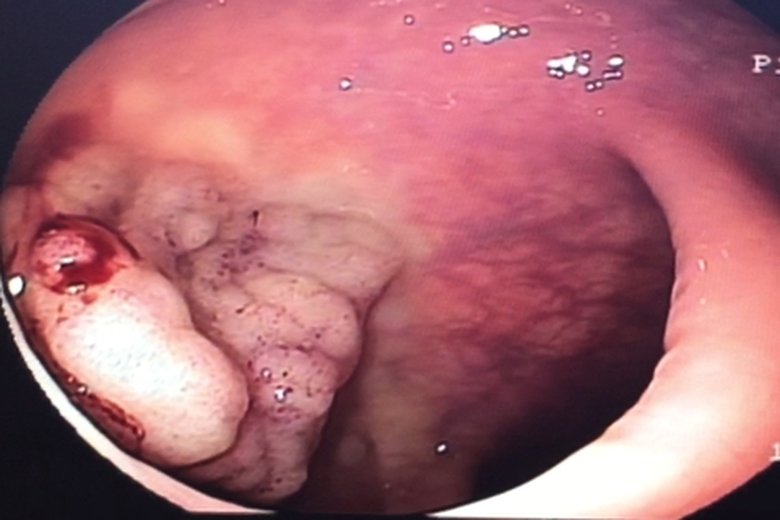

內視鏡切除瘜肉免動刀

醫生操作時將一根導管與攝像儀探入大腸內,以查看大腸內部的狀況。圖為內視鏡光源照射瘜肉組織外觀(衛福部朴子醫院提供)

【新唐人亞太台 2015 年 12 月 11 日訊】家族有患大腸瘜肉,或家族史患有大腸癌或線性瘜肉,是罹患大腸癌的高危險群。大腸瘜肉演變為大腸癌之前症狀不明顯,除非瘜肉已經大於1公分或已到晚期才會出現不適的症狀。大腸內視鏡做檢查,可早期發現大腸性瘜肉並切除,有效降低大腸癌的發生率。

國民健康署2011年最新癌症統計,男女性大腸癌發生率多在40歲以後,大腸癌在55-64歲年齡層為發病高峰,原因是飲食西化,外食比率高、多油、多肉、低纖維的食物。大腸癌在零期或一期的治療研究顯示,存活率可以高達百分之80以上。定期大腸鏡檢查是預防大腸癌的不二法門。

50歲以上成人最好定期至醫院作糞便篩檢及大腸鏡檢查。若有1.血便、肛門出血或黏液變多;2.排便習慣改變、便秘或腹瀉;3. 排便不乾淨或有便意但排不出;4.體重驟減等,應盡速至醫院就診尋求專業醫師診治。